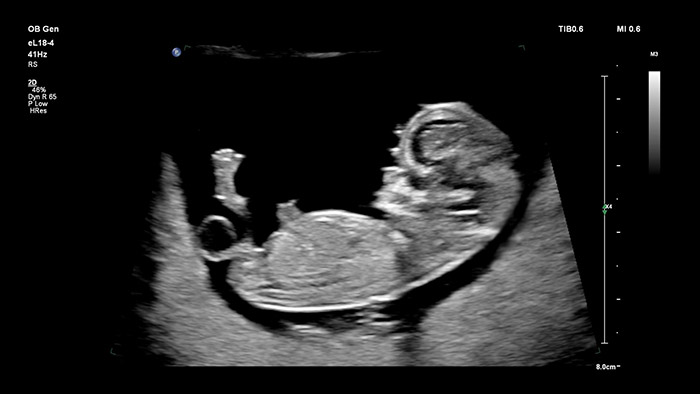

Sonde eL18-4 de Philips

Résolution et pénétration de qualité supérieure :

La sonde Philips eL18-4 dotée de la technologie MicroFlow Imaging repousse les obstacles grâce à l’imagerie 2D haute résolution et à la détection ultra-sensible du débit sanguin qui permettent d’évaluer la santé globale du fœtus dès le début de la grossesse, où une résolution et une fiabilité de diagnostic irréprochables sont essentielles. Extrêmement polyvalente, la sonde V9-2 est spécialement conçue pour les applications obstétricales et utilise la puissance de la technologie de cristal PureWave pour offrir une imagerie 2D et 3D de haute qualité, tout en restant légère pour sa catégorie.